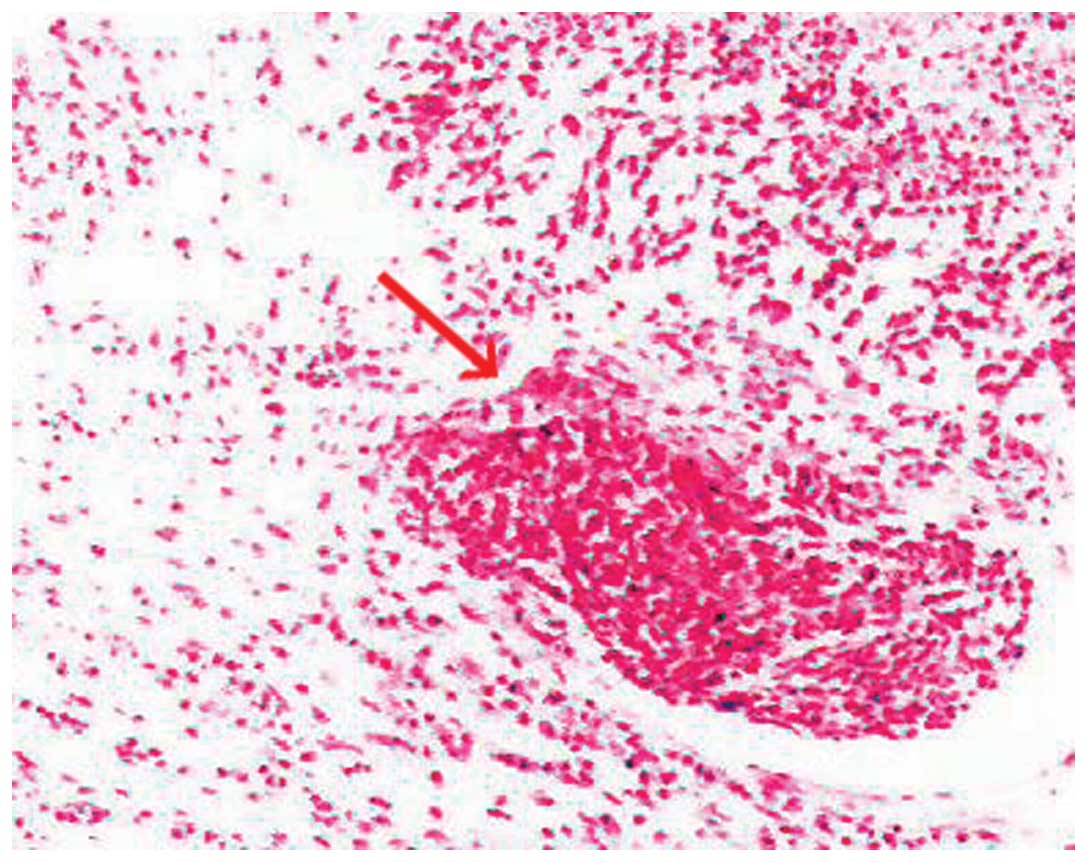

Figure 4.

Histopathological examination of the cervical lymph node biopsy specimen, confirming the diagnosis of small-cell lung cancer (arrow) (hematoxylin and eosin staining, magnification x100).

A neurological examination revealed proximal muscle weakness and absence of deep tendon reflexes. The cranial nerve, cerebellar and sensory functions were all normal. The laboratory tests revealed hyponatremia and hypochloremia. The electromyogram suggested neurogenic damage (Bilateral abductor muscle and peroneus longus, potential loss of the median nerve, the common peroneal nerve, and mild slowing of the motor conduction velocity of the tibial nerve). A repetitive nerve stimulation test performed on the right median nerve revealed a decremental response to the electrical stimulation. An experiment with neostigmine supported the presence of postsynaptic membrane lesions. Repeated nerve stimulation of 7 Hz lead to an increased response, whereas repeated nerve stimulation of 15 Hz was associated with decreased response (Fig. 1). The findings of magnetic resonance imaging scans of the brain and lumbar vertebra were normal. The preliminary diagnosis of the patient's condition was MG. However, treatment with hypertonic saline and fluid restriction, as well as low-dose corticosteroid therapy for MG, did not improve the symptoms. After referring to several studies in the literature (6–8), LEMS was taken into consideration. The levels of tumor markers, including carcinoembryonic antigen and neuron-specific enolase, were found to be abnormal. An ultrasound of the superficial lymph nodes identified an enlarged lymph node in the right cervical region, sized 1.5×0.9 cm (Fig. 2). Chest computed tomography (CT) images revealed a 1.6-cm mass in the superior lobe of the right lung, associated with a small amount of pleural effusion (Fig. 3). A right cervical lymph node biopsy was conducted; on pathological immunohistochemical examination, the lesion was found to be positive for epithelial membrane antigen (+), CD56 (+), thyroid transcription factor-1 (+), creatine phosphokinase (+) and Ki67 (+++) and negative for synaptophysin and leukocyte common antigen. Combined with the findings of the histopathological analysis (hematoxylin and eosin staining; Fig. 4), the diagnosis was eventually confirmed as SCLC combined with LEMS.